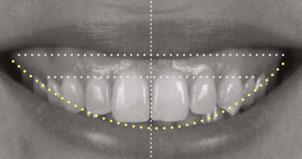

Patient A.M., age 28, presented with excessive gingival display she wished to correct (Figure 3). She lives in Boston and was willing to travel 3 hours each way to our practice in Queens,

New York. Multiple orthodontists near her home had prescribed surgical intervention for her case, but she had seen a gummy smile patient of mine treated nonsurgically and was excited about the prospects for herself (Instagram @NYCorthodontist).

Diagnosis

Mesocephalic in CL 1 occlusion with slight constriction in the posterior areas. The patient’s facial and cephalometric analysis appeared normal, and her facial thirds were well balanced. Looking closely at the Digital Smile Design Analysis (Figure 3), we can appreciate the excessive gingival display, ranging between 4 mm-6 mm in the posterior and 3 mm-4 mm in the anterior.

Maintain CL I occlusion. Develop the transverse relationships, eliminate the posterior negative root torques, and resolve the excessive gingival display via full-arch nonsurgical impaction. All vertical changes would be accomplished using only Angel Aligner, TADs, and elastics. Her maxillary lateral incisors may later require buildups to improve the Golden Proportion of the anterior teeth. My iOrtho software setup for maxillary intrusion was to place angelButtons (blue) between the U2s-3s, U4s-5s, and distal of the U6s (Figure 4).